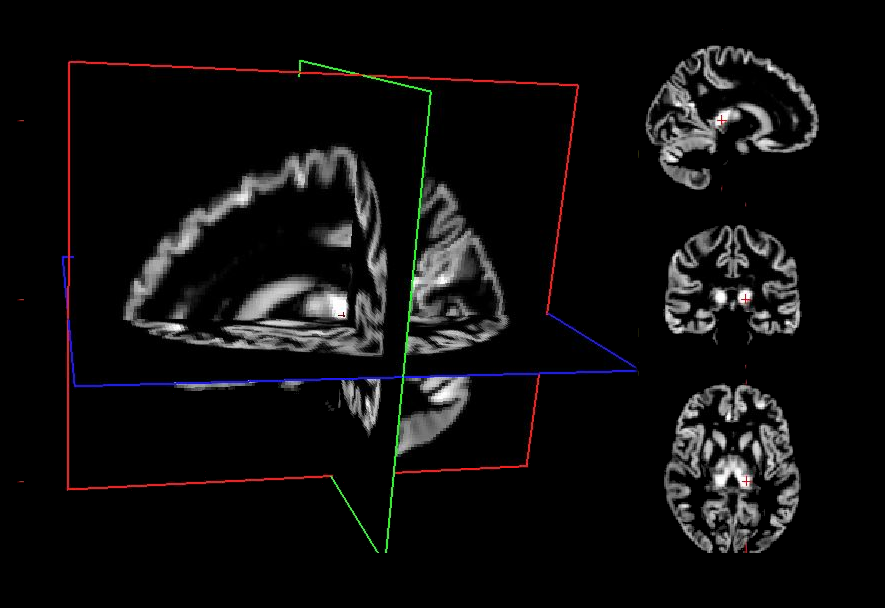

7. Voxel Based Morphometry Workflow

Voxel-Based Morphometry (VBM) is a widely used neuroimaging technique for assessing structural differences in brain anatomy across individuals or groups. It provides an automated, whole‑brain approach to quantifying regional gray matter (GM), white matter (WM), and cerebrospinal fluid (CSF) volumes from T1-weighted MRI scans. Unlike manual or region‑of‑interest methods, VBM does not require predefined anatomical boundaries, making it particularly well suited for exploratory analyses and large-scale studies.